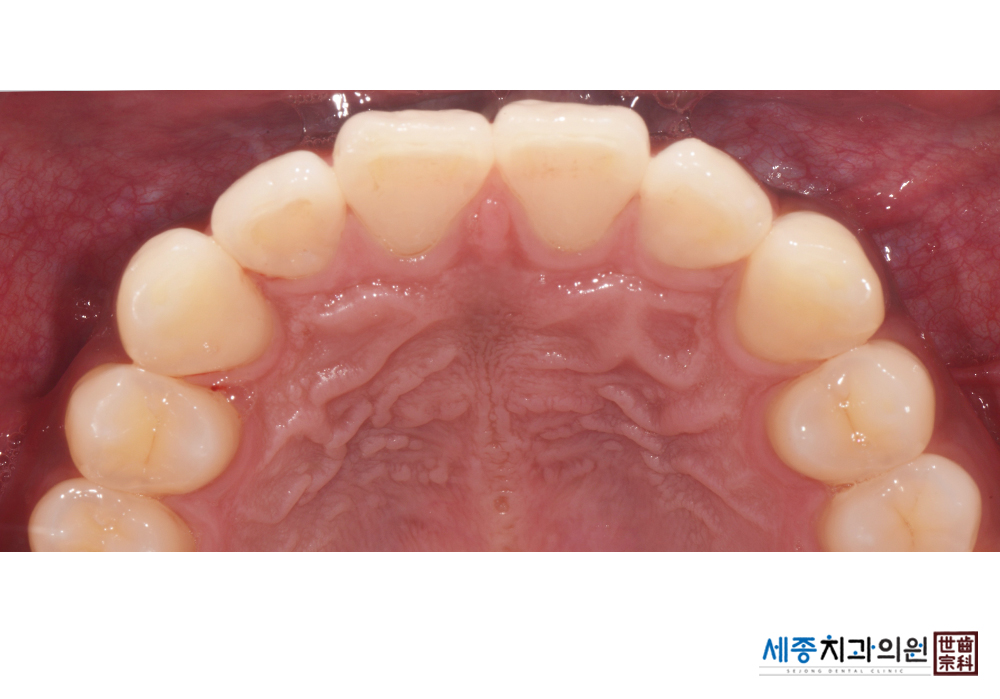

[스케일링] 치주질환 예방 스케일링

치료전 : 2020-01-24

치료후 : 2020-01-24

가글마취&저주파 스켈러를 사용한 스케일링